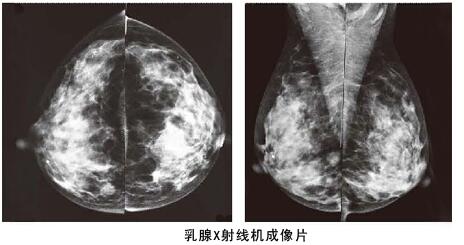

其實(shí)相比乳腺彩超,利用數(shù)字化鉬靶乳腺機(jī)對(duì)于乳腺管較細(xì)或者乳腺本身存在問(wèn)題,可以進(jìn)行更加細(xì)致檢查,而且它是女性乳腺癌早期診斷的金標(biāo)準(zhǔn),數(shù)字化鉬靶乳腺機(jī)可以發(fā)現(xiàn)0.1毫米的鈣化點(diǎn),提示癌前病變。是各種乳腺疾病檢查的必備醫(yī)療設(shè)備:如乳腺炎癥,乳腺增生,乳腺纖維瘤,乳腺囊腫等。對(duì)于一些年齡較大的女性來(lái)說(shuō),數(shù)字化鉬靶乳腺比乳腺彩超檢查更加的準(zhǔn)確。